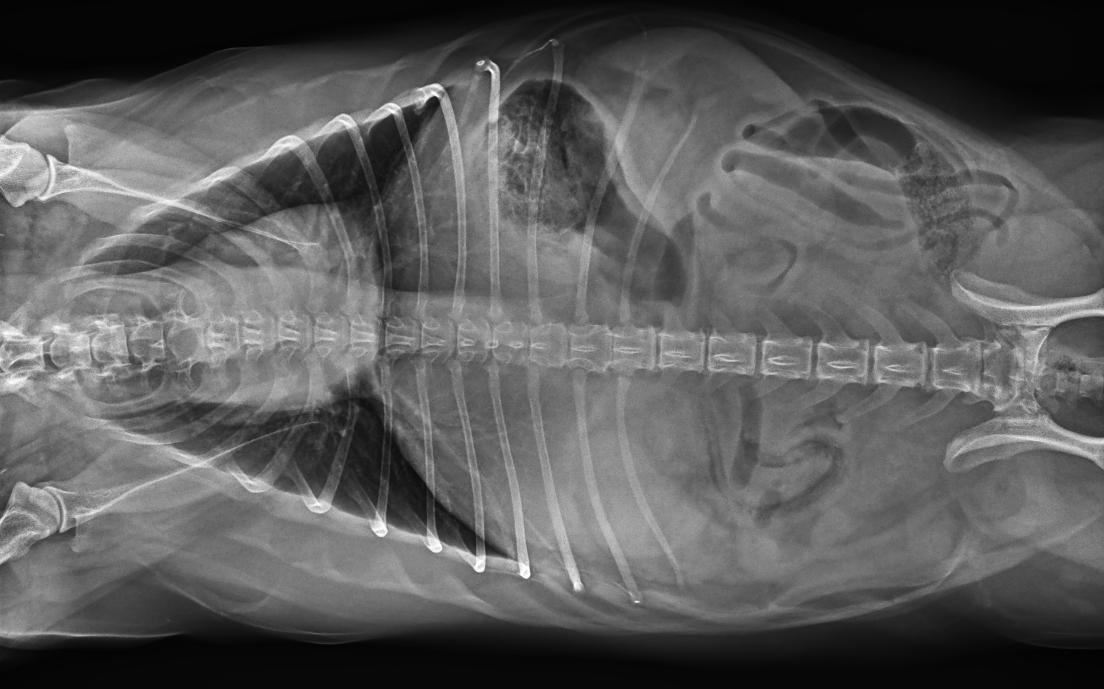

專為拍攝寵物設(shè)計 VET1900 寵物DR

● 17*17大尺寸平板探測器,獲得高質(zhì)量圖像

● 優(yōu)異的空間分辨率及信噪比,提升圖像質(zhì)量

● 進(jìn)口高品質(zhì)球管,大功率、高熱容量、微焦點(diǎn),1.0/2.0mm雙焦點(diǎn)設(shè)計

● 25kHz高主逆變頻率,輸出電壓更穩(wěn)定;瞬時定格影像,無拖尾現(xiàn)象